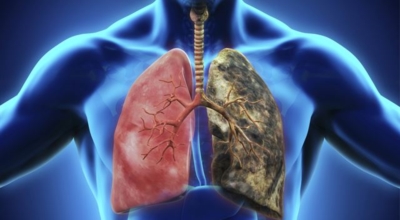

폐렴은 폐의 감염으로 인해 발생해요. 대부분의 감염은 박테리아나 바이러스에 의해 발생하지만 종종 원인을 찾을 수 없어요. 감기나 독감에 의해 유발될 수 있고, 이로 인해 세균이 폐에 접근할 수 있어요. 세균성 폐렴은 폐렴구균 박테리아에 의해 발생할 수 있어요. 이것은 가장 심각하고 잠재적으로 생명을 위협하는 유형의 폐렴 중 한가지이예요.

폐렴을 유발하는 다른 유형의 박테리아는 헤모필루스 인플루엔자와 모락셀라 카타랄리스 이지요. 바이러스성 폐렴은 여러가지 바이러스에 의해 발생해요. 가장 흔한 것은 인플루엔자 바이러스, 인간 아데노바이러스 또는 호흡기 세포융합 바이러스이지요.